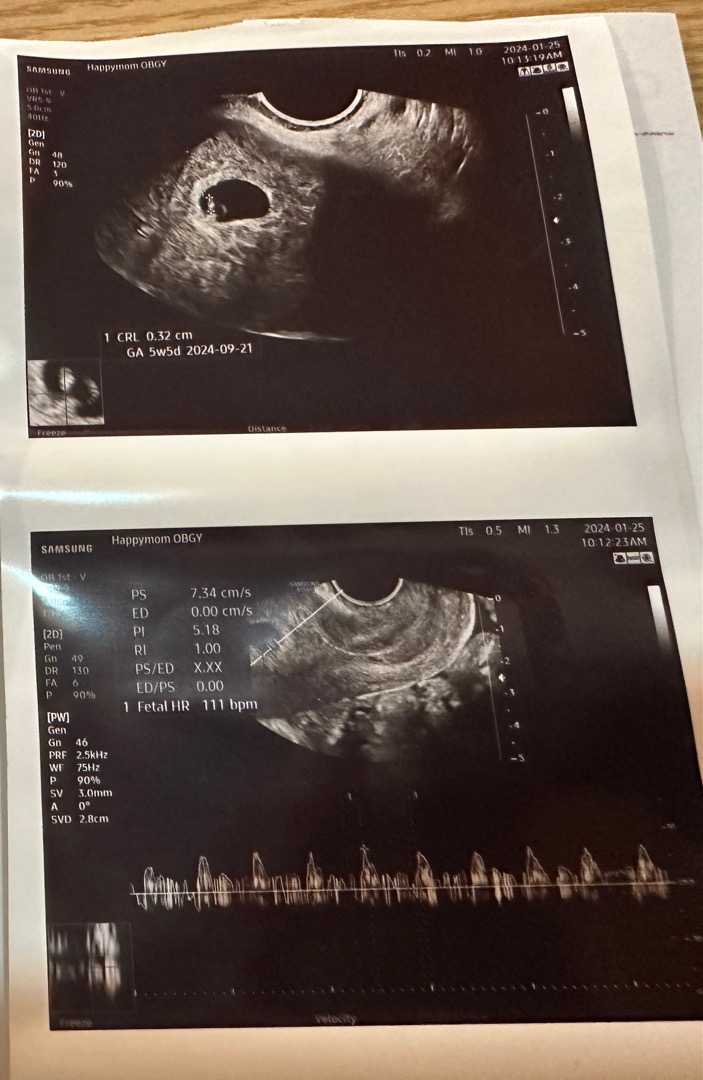

5주4일 심소듣고왔어요🩷

진짜콩알만하네요 .. ㅎㅎ 오늘 5주4일찬데 우렁차게 울리는 111bpm의 심장소리 듣고 왔어요😉

네 ㅎㅎ 착상이빨리된거같아요 아기집크기는 안재주시고 아가만 재주셨어요◡̈

감사합니다 아기크기만 재주셨어요 .. ㅎㅎ!